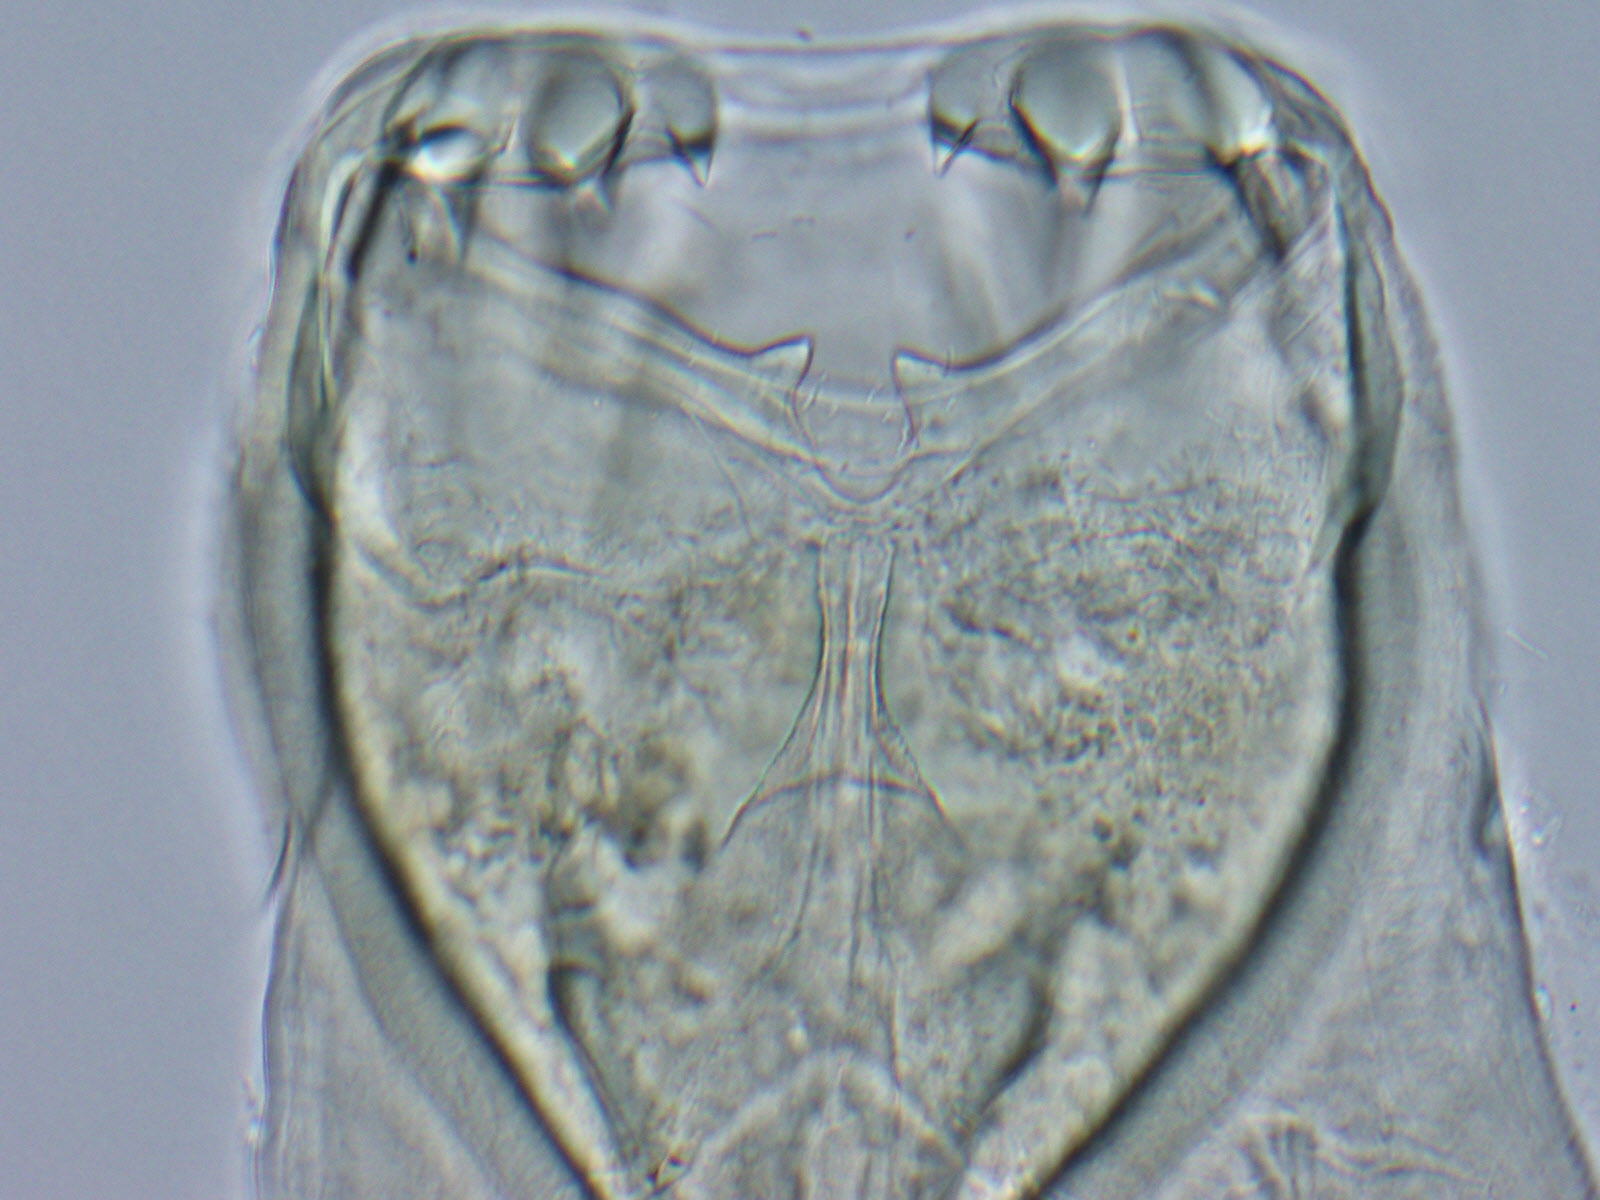

They use their hooklike mouths to latch onto an animal's intestines, where they feast on tissue fluids and blood. Infected animals can experience dramatic weight loss, bloody stool, anemia and lethargy, among other issues.